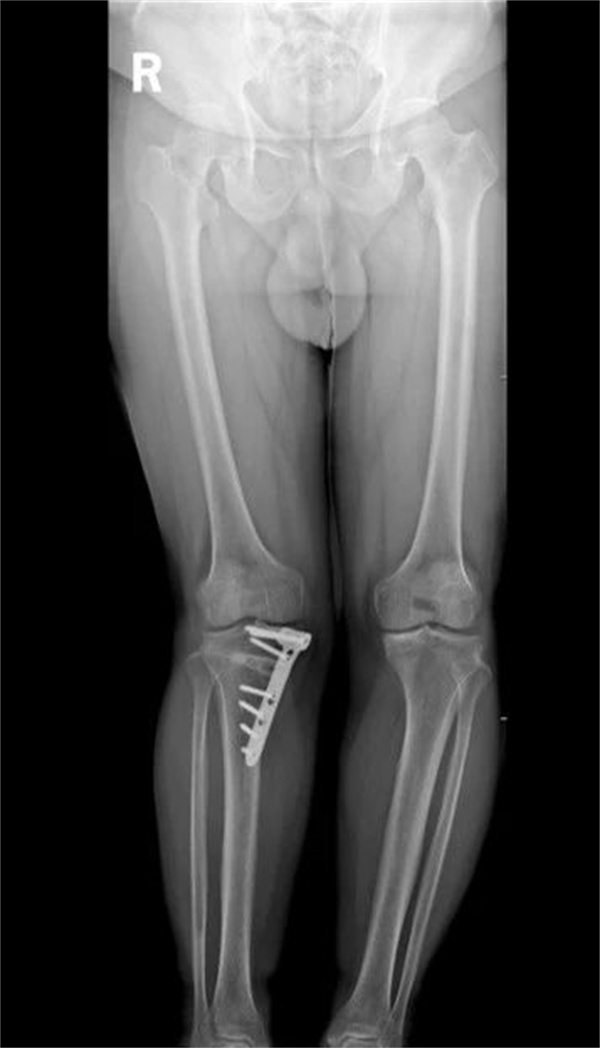

术前下肢全长片

一个月前,47岁的李先生双膝关节活动后疼痛3年,半年前于外院诊断为“原发性膝骨关节病、后天性膝内翻畸形”,接受右胫骨内侧高位截骨术治疗,术后右膝疼痛有所缓解,但肢体外观明显外翻。近1月,李先生感觉左膝关节疼痛加重,坐位站起、行走及上下楼困难,听闻航空总医院骨关节科副主任李兵团队在诊治膝关节骨关节炎、矫形手术方面有丰富经验,随即慕名就诊。

李兵经过详细的病史询问、专科查体和影像学检查,结合患者自身情况综合评估,考虑到患者尚年轻,对日常活动有一定要求,并且患者体重(105千克)较大,膝关节关节负担更重,截骨术对下肢整体力线的矫正角度控制要求高,容易产生过度矫正或矫正不足现象,决定为患者实施AI术前规划+3D打印导板辅助下的左侧胫骨高位截骨术。